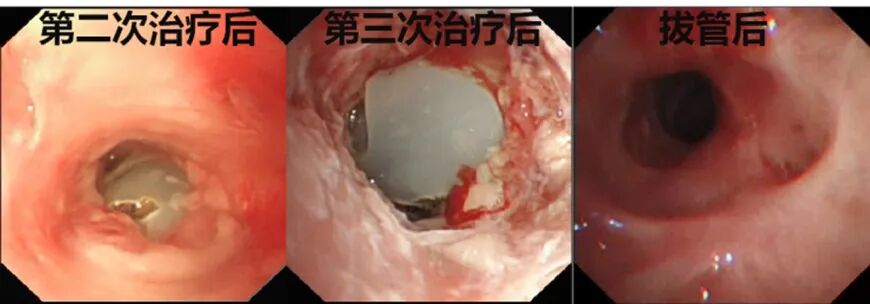

完成术前评估后,马上进行第一次气管镜,在方苏榕主任的指导下,呼吸介入医师常立功迅速完成气道评估,发现声门下2.5cm处气管闭塞,肉芽组织增生伴瘢痕形成,无法进镜,医生使用电圈套器和激光清理肉芽和瘢痕组织,后使用冷冻和球囊扩张再通狭窄气管,最后局部使用糖皮质激素抑制肉芽组织增生。

术后,小张感觉呼吸较前好转。为了达到更好的治疗效果,方苏榕和常立功医师一鼓作气连续完成3次气管狭窄再通术,小张终于可以简单发音。再次经过联合会诊和综合评估,在完成24小时的堵管后,成功拔除小张的气管切开套管。